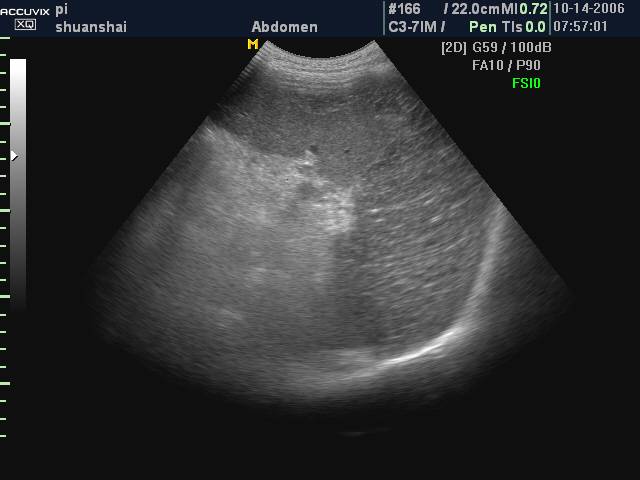

二维超声图像

1、单纯性脾囊肿 有一般囊肿的特点

4、假性脾囊肿 血肿吸收机化后的囊肿 壁形态可不规则,内可见强回声斑点及条索

单纯性脾囊肿:

假性脾囊肿: